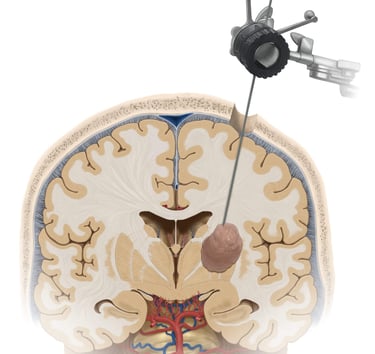

Biopsias cerebrales

Procedimientos de mínima invasión para diagnóstico de enfermedades neurológicas.